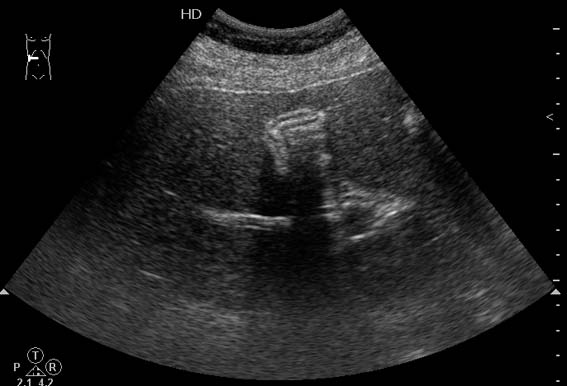

Похожий случай. Молодой мужчина, врач, длительные терпимые боли в правом подреберье.

???

2.По второму случаю можно было бы просто подумать о гиперкинезии ж.пузыря,который сокращается и "от глотка слюны".Но,прочитав эту фразу:"In patients with hilar cholangiocarcinoma and complete obstruction of both rigt and left hepatic ducts,extrahepatic bile ducts and the gollbladder appear empty(colapsed)",учитывая сложность выявления "малых" опухолей печени методом УЗИ,я думаю,что надо сделать КТ.